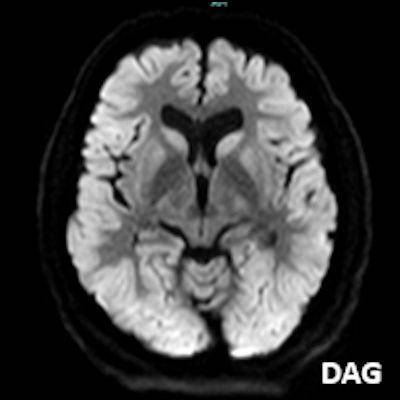

- A) Bilateral serebral kortekste (oklar) ve bazal ganglionlarda (oklar) yaygın DAG hiperintens, ADC hipointens difüzyon kısıtlamaları görülüyor.

- B) 9 gün sonraki difüzyon MR incelemede kortikal ve bazal ganglionlardaki difüzyon kısıtlamalarının gerilediği, bilateral serebral beyaz cevherde (oklar) ve internal kapsül arka bacağı- kortikospinal trakt boyunca (oklar) yaygın DAG hiperintens, ADC hipointens difüzyon kısıtlamalarının geliştiği izleniyor.

- T2A / FLAIR serilerde beyaz cevherde özellikle sentrum semiovalede diffüz yüksek sinyal görülür. Subkortikal U lifleri sıklıkla korunur.

- DAG görüntülemede sıklıkla belirgin difüzyon kısıtlaması görülür.